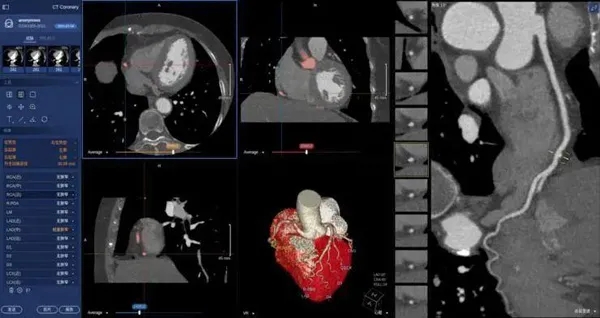

在醫(yī)學(xué)領(lǐng)域,機器視覺主要用于醫(yī)學(xué)輔助診斷。首先采集核磁共振、超聲波、激光、X射線、γ射線等對人體檢查記錄的圖像,再利用數(shù)字圖像處理技術(shù)、信息融合技術(shù)對這些醫(yī)學(xué)圖像進(jìn)行分析、描述和識別,最后得出相關(guān)信息,對輔助醫(yī)生診斷人體病源大小、形狀和異常,并進(jìn)行有效治療發(fā)揮了重要的作用。不同醫(yī)學(xué)影像設(shè)備得到的是不同特性的生物組織圖像,如X射線反映的是骨骼組織,核磁共振影像反映的是有機組織圖像,而醫(yī)生往往需要考慮骨骼有機組織的關(guān)系,因而需要利用數(shù)字圖像處理技術(shù)將兩種圖像適當(dāng)?shù)丿B加起來,以便于醫(yī)學(xué)分析。